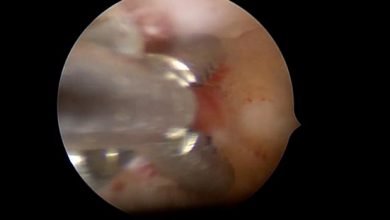

vNotes Hysterectomy – Cihan Kaya

Septum Rezeksiyonu

Tubal Polip

Vajinal Asiste Laparoskopik Seklaj Pektohisteropeksi – Dr. Çağlar Çetin

LİGHTED LS HİSTEREKTOMİ – Op. Dr. Seda ŞAHİN AKER